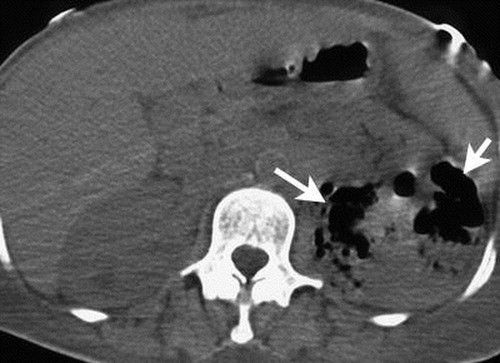

is this mass enhancing?

yes!

new finding. Management?

excise it